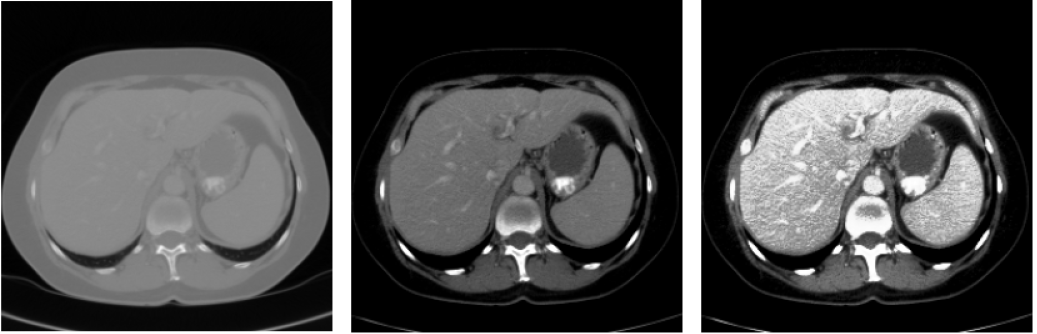

相关图片展示: